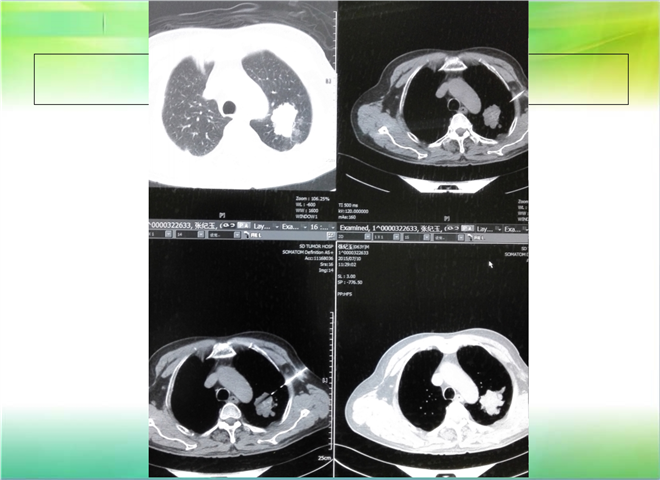

CT引导下穿刺活检术